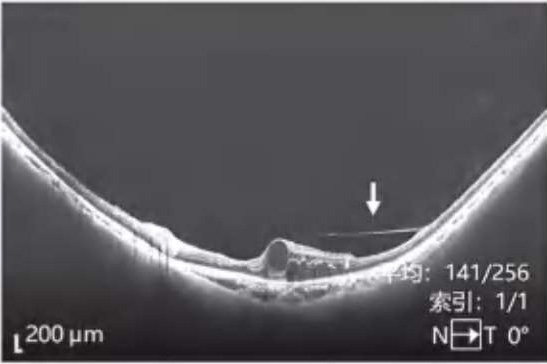

图2-2-1 抗VEGF及PRP治疗后玻璃体后脱离范围显著扩大的PDR案例

A.PDR合并玻璃体视网膜牵拉引发的相关DME,既往已行PRP,行4次抗VEGF药物治疗后,黄斑区玻璃体后界膜与视网膜分离(白色箭头所示),玻璃体视网膜牵拉解除,黄斑水肿较前明显好转。B.PDR合并玻璃体视网膜牵拉性相关DME,在行3次视网膜激光光凝治疗后,黄斑区玻璃体后界膜与视网膜分离(白色箭头所示),玻璃体视网膜牵拉缓解,黄斑水肿较前好转。